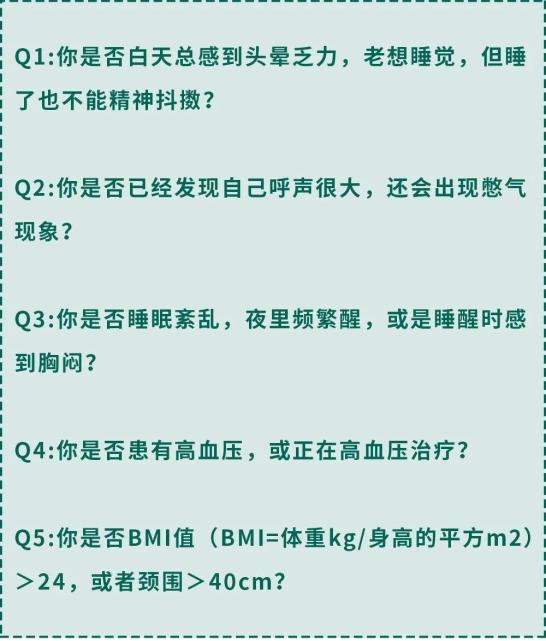

不放过任何一个小毛病! 我给老爷们整理了一些方法。对自己,你可以做下这个自测表:

我给老爷们整理了一些方法。对自己,你可以做下这个自测表: 如果上面超过三个回答“是”

如果上面超过三个回答“是”很有可能就是“睡眠呼吸暂停综合征”!

对他人,你可以帮对方看看: 发现不对劲的朋友们,请一定要重视起来。